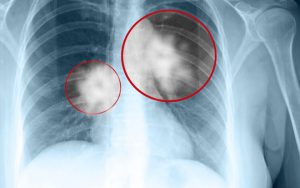

Ung tuyến giáp di căn phổi là hay còn gọi là ung thư tuyến giáp ...